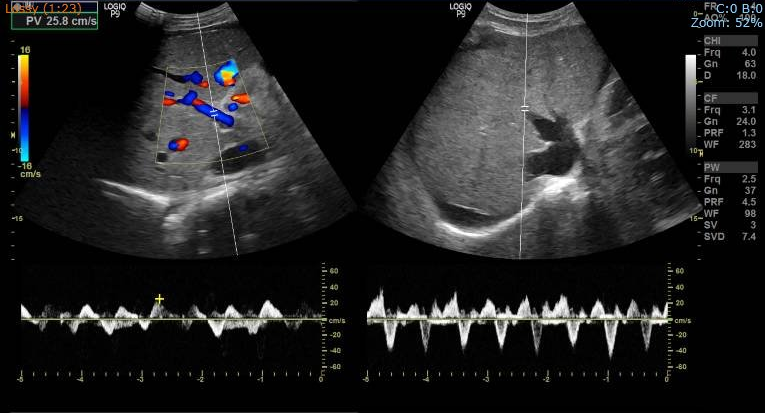

Hepatofugal flow